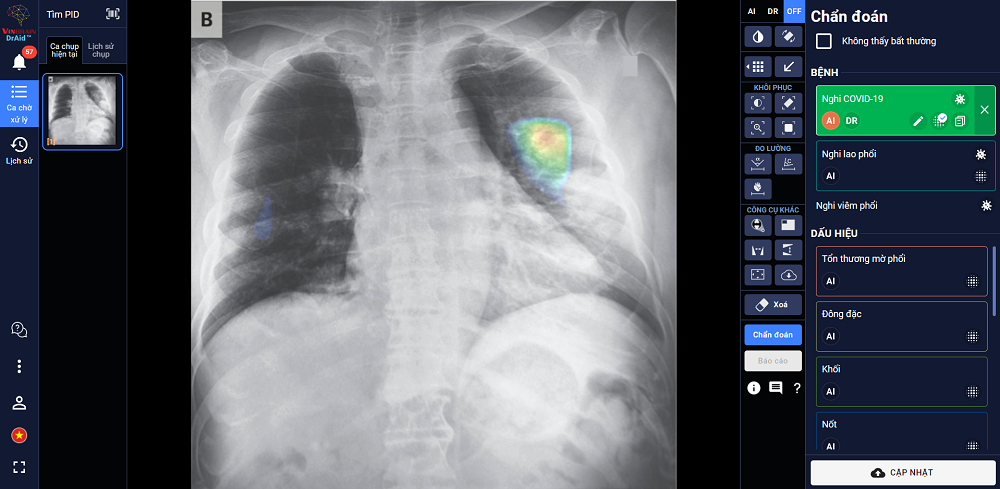

“DrAid for Radiology” - AI trợ lý bác sĩ cho chẩn đoán hình ảnh y tế là sản phẩm đầu tay của VinBrain và cũng là sản phẩm AI hoàn chỉnh đầu tiên của y tế Việt Nam ra mắt phiên bản đầu tiên vào ngày 14/06/2020. Sản phẩm có khả năng phát hiện, sàng lọc trên 21 dấu hiệu bất thường và bệnh lý về "phổi - tim - xương" trong vòng 5 giây với độ chính xác trên 89%; đồng thời có thể chia sẻ kết quả chẩn đoán thông qua QR code hoặc đường link.

Đặc biệt, sản phẩm có khả năng tự cảnh báo COVID-19, kể cả các trường hợp không có triệu chứng hoặc tổn thương phổi nhẹ dựa trên X-quang ngực thẳng, kết hợp cùng xét nghiệm PCR giúp nâng cao độ chính xác, giảm thiểu tình trạng âm tính giả,... DrAid cũng nổi bật với tính năng “Hỏi ý kiến Bác sĩ thứ 2 (từ xa)”. Thông qua việc chia sẻ hình ảnh trực tiếp từ DrAid, bác sỹ có thể hội chẩn từ xa với đồng nghiệp hoặc tham khảo ý kiến của các chuyên gia đầu ngành mà không bị ảnh hưởng bởi rào cản địa lý.

DrAid được ban giám khảo ACM SIGAI đánh giá cao vì sản phẩm đã kết hợp và ứng dụng những kỹ thuật tiên tiến nhất trong lĩnh vực trí tuệ nhân tạo như phân loại nhiều lớp, suy luận theo cấu trúc cục bộ đến tổng quan, học chủ động, đào tạo đối nghịch, mạng nơ ron tích chập phức hợp, nhận dạng giọng nói cho chỉnh sửa báo cáo y tế tự động, khoanh vùng tổn thương trên ảnh y tế với kiến thức máy học sử dụng công nghệ cao AI dựa trên mô hình với hàng trăm triệu tham số điểm ảnh (pixel) và dữ liệu lớn hàng triệu ảnh với mỗi ảnh có hàng triệu điểm ảnh (pixel), cùng nhiều kỹ thuật khác tạo nên một dịch vụ trí tuệ nhân tạo phục vụ y tế toàn diện.